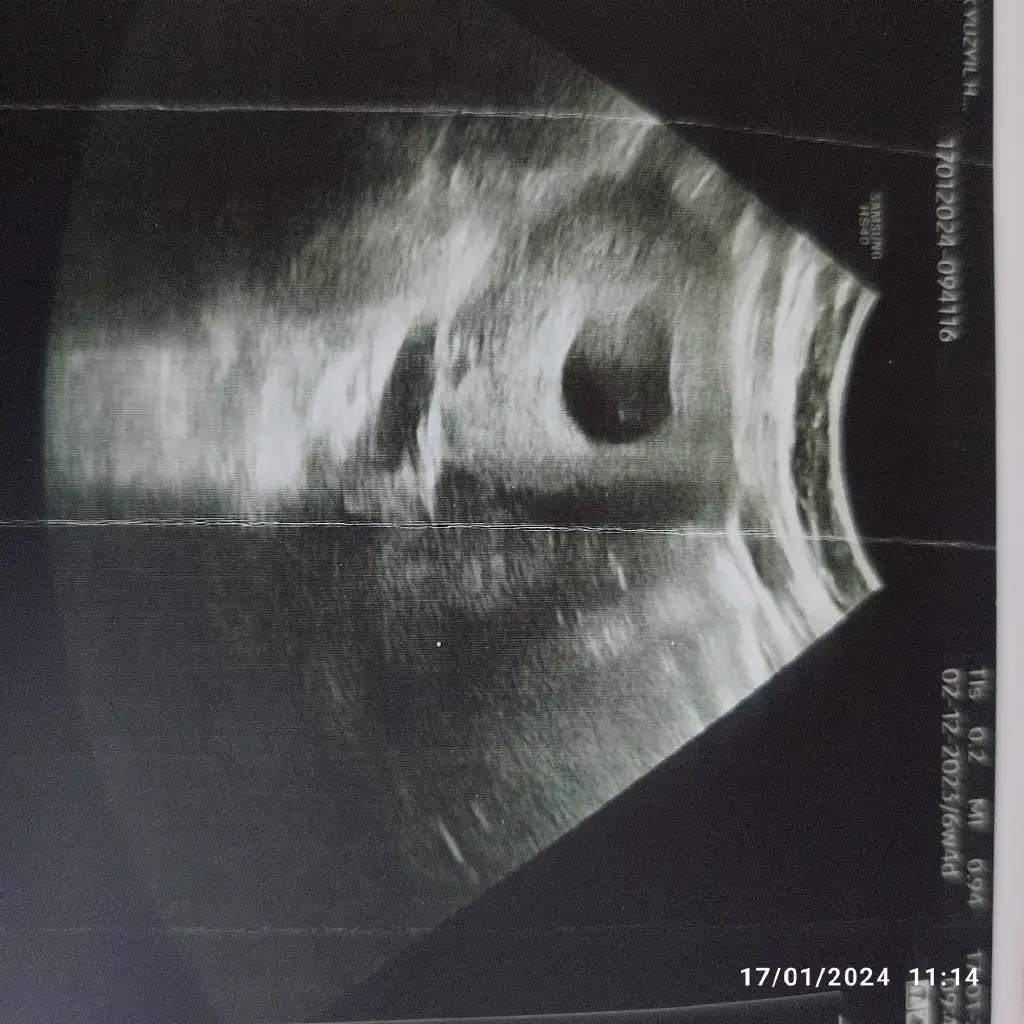

Ay kuşuuuuum ay niye bilmiyorum senin ultrasonun beni ağlattı sevinçten çok küçük kıyamam ben ona . Maşallah sana da ona da küçük noktan büyüsün sağlıkla kucağına alasın inşallah.Bu sabah ben de minnosumu gördüm çok şükür. Daha çok küçük dedi alttan muayane yapmadı direk karından baktı. Kesenin içinde nokta gibi gözüken beyaz şey sen nasıl bu kadar bulantı yapabiliyorsun söyle bana

Kalp atışı da duyuldu mu erken mi bilmiyorum da merak ettim 6 haftada herhaldeBu sabah ben de minnosumu gördüm çok şükür. Daha çok küçük dedi alttan muayane yapmadı direk karından baktı. Kesenin içinde nokta gibi gözüken beyaz şey sen nasıl bu kadar bulantı yapabiliyorsun söyle bana

Çok sevindim canım gözün aydınBu sabah ben de minnosumu gördüm çok şükür. Daha çok küçük dedi alttan muayane yapmadı direk karından baktı. Kesenin içinde nokta gibi gözüken beyaz şey sen nasıl bu kadar bulantı yapabiliyorsun söyle bana